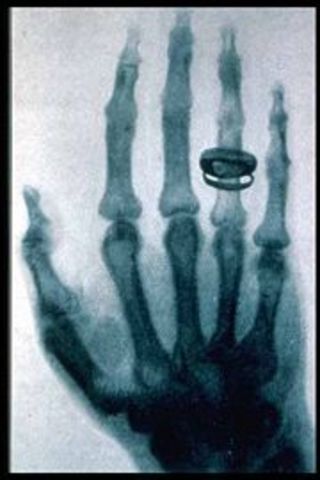

X-rays

Wilhelm Roentgen, a German professor of physics, was the first person to discover electromagnetic radiation in a wavelength range commonly known as X-rays today.